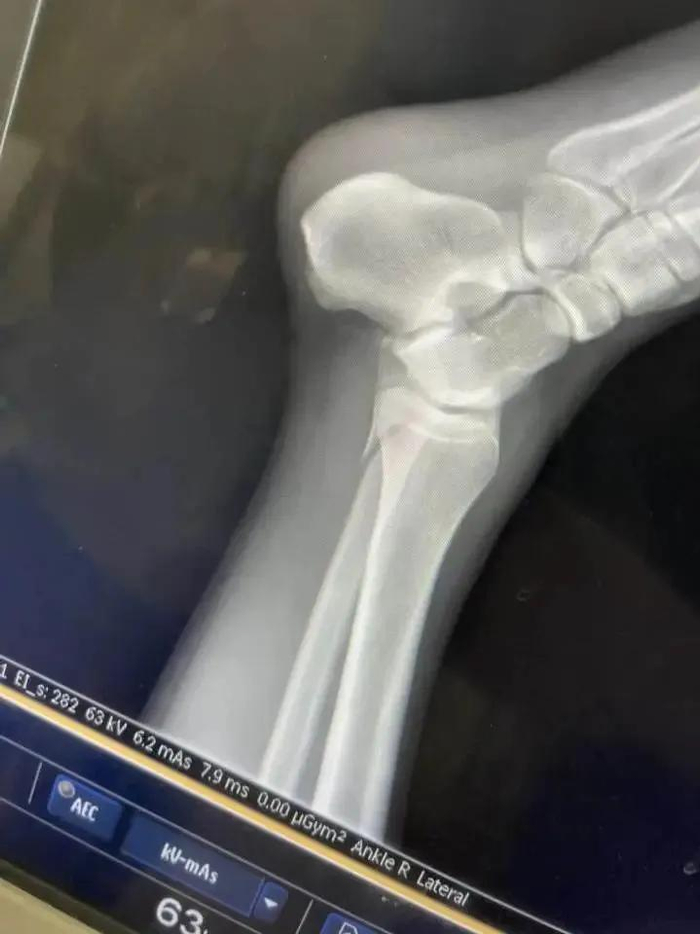

“我感觉水下有个不平的东西,当时一瞬间还没感觉脚崴了,硬撑着走上岸就走不动了,最后用一只脚蹦到救护车上。”

“我就把躺的位置让给她,她的腿骨折了,我是踝骨受伤。现场的工作人员让我们到二级以上的公立医院治疗,然后报销。”

“医院建议我动手术,我当时打算先保守治疗,因为还年轻,不能因为这点事儿动刀。”